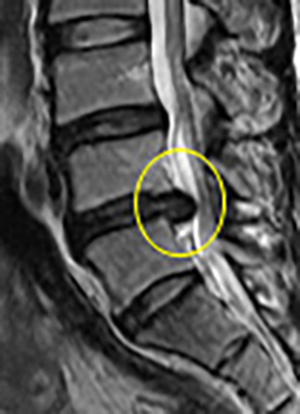

척추와 뼈 사이에 위치한 이 디스크는 외부로부터의 물리적 충격을 완화하고 단단한 뼈가 직접 충돌할 때 문제가 발생하지 않도록 하는 탄성이 높은 구조입니다. 외부의 영향이나 잘못된 위치로 인해 디스크가 꺼지면 염증이 발생하고 신경이 눌려 요통과 요통이 발생합니다. 기술적으로는 요추 디스크 분리라고 하며 일반적으로 요추 디스크 고장이라고 합니다.